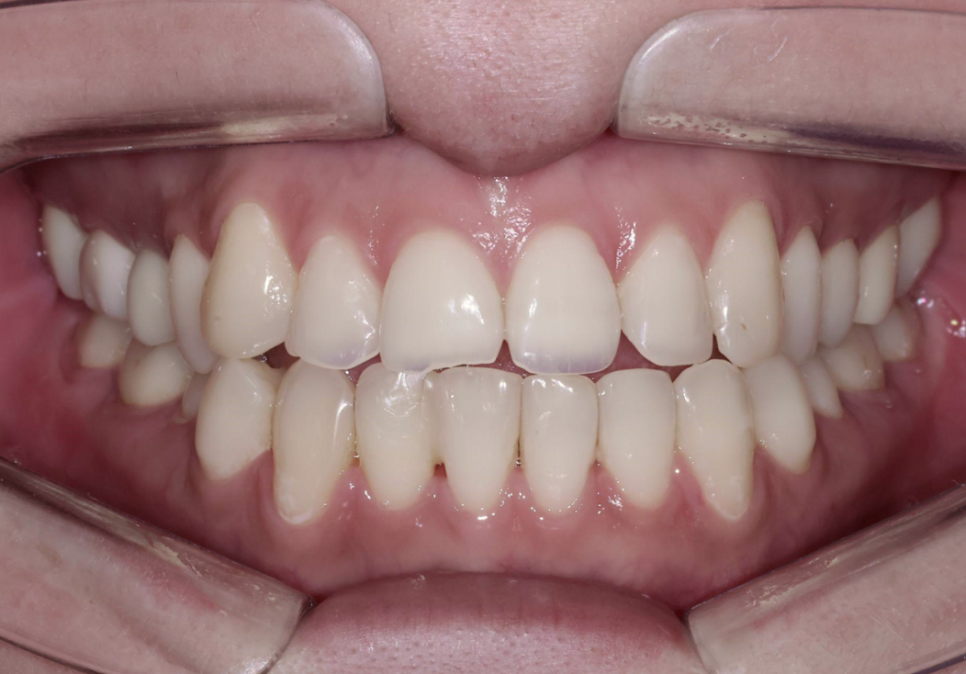

시술 결과 - 보철물 부착 후

8개 앞니에 올세라믹 크라운을 부착한 후의 결과를 보여드리겠습니다.

8전치 올세라믹 크라운 부착 직후

부착 직후 사진을 보시면, 잇몸과 보철물의 경계가 자연스럽게 이어지고 주변 잇몸 상태도 안정적인 것을 확인할 수 있습니다. 절단면이 균일하고 가지런하게 정리되었고, 이전에 돌출되어 있던 오른쪽 위 송곳니도 자연스러운 치열 배열을 이루게 되었습니다.

윗 앞니가 아랫 앞니를 약 1mm 덮는 정상적인 교합 형성

교합을 확인해 보면, 치료 전에는 윗 앞니가 아랫 앞니를 충분히 덮지 못했는데, 이제는 약 1mm 정도 자연스럽게 덮어주는 정상적인 교합이 형성된 것을 볼 수 있고, 교합 안정성도 양호하게 유지되고 있습니다.

무엇보다 환자분의 스마일 라인이 확실히 개선되었습니다. 웃을 때 치열이 가지런하고 자연스러운 곡선을 이루면서, 전체적인 인상이 훨씬 깔끔하고 밝아지셨습니다.